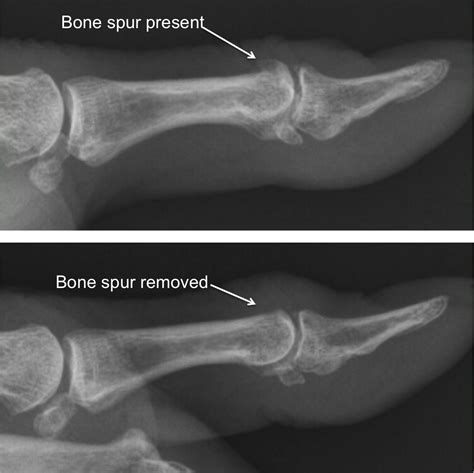

• Imaging tests: X-rays, CT scans, or MRI scans to visualize the bone spur and assess its size and location.

• Arthroscopic surgery: A minimally invasive procedure to remove the bone spur using small incisions and specialized tools.

• Open surgery: A more invasive procedure that involves making a larger incision to access and remove the bone spur.